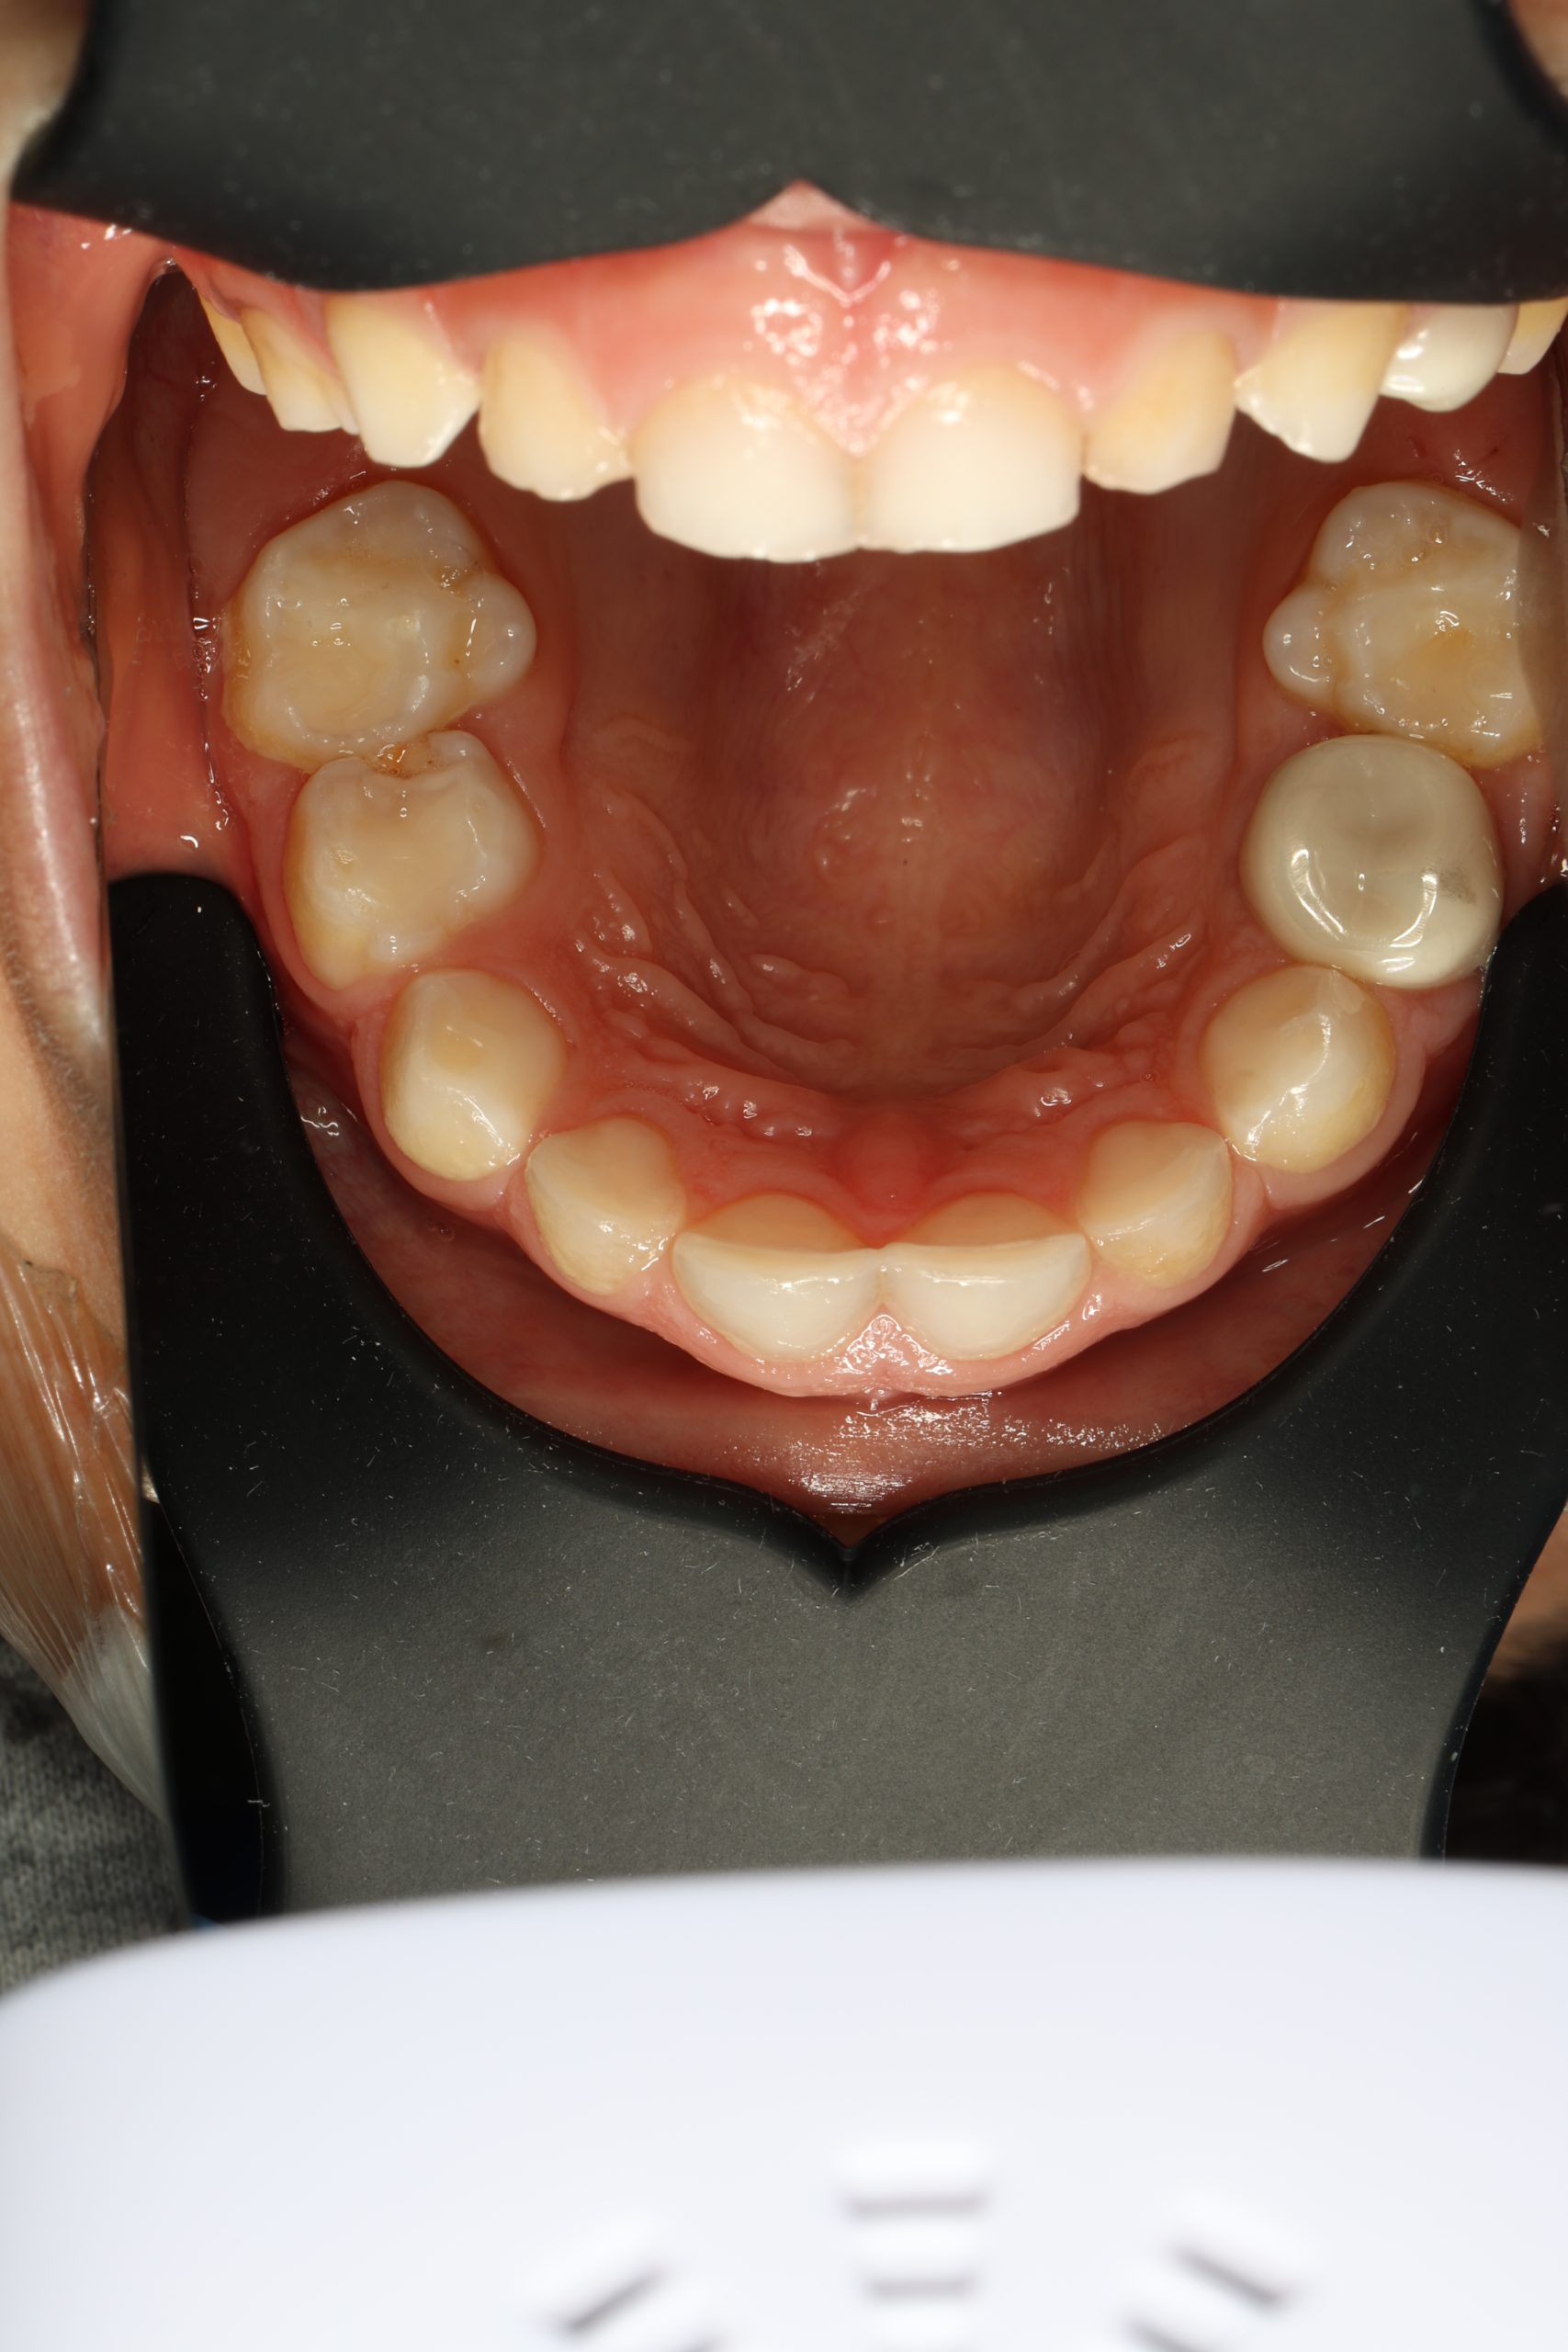

Inside every tooth lies a narrow chamber that contains nerves and blood vessels — the dental pulp. When deep decay, a leaking filling, or trauma allows bacteria to reach this inner space, the pulp becomes inflamed and then infected. The result is pressure, sensitivity, and often an unmistakable throbbing pain.

Signs You Might Need Root Canal Therapy

- Persistent sensitivity to hot or cold

- Pain when chewing or releasing the bite

- Throbbing pain at night

- A small bump on the gum near the tooth